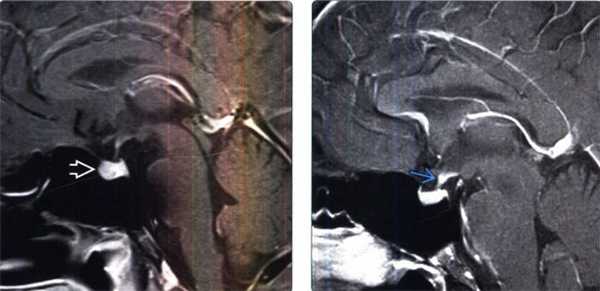

(Слева) МРТ, постконтрастное Т1-ВИ, сагиттальный срез: у мужчины 37 лет с пангипопитутаризмом на фоне лечения ипилимумабом по поводу метастатической меланомы отмечаются относительно крупные размеры гипофиза. По сравнению с предыдущей МРТ, проведенной шесть недель назад, размеры железы увеличились вдвое. Такая картина согласуется с лекарственно-индуцированным гипофизитом.

(Справа) МРТ, постконтрастное Т1-ВИ, сагиттальный срез: у пациента в возрасте 50 лет с несахарным диабетом определяется локальное утолщение воронки гипофиза, обусловленное лимфоцитарным инфундибулонейрогипофизитом.